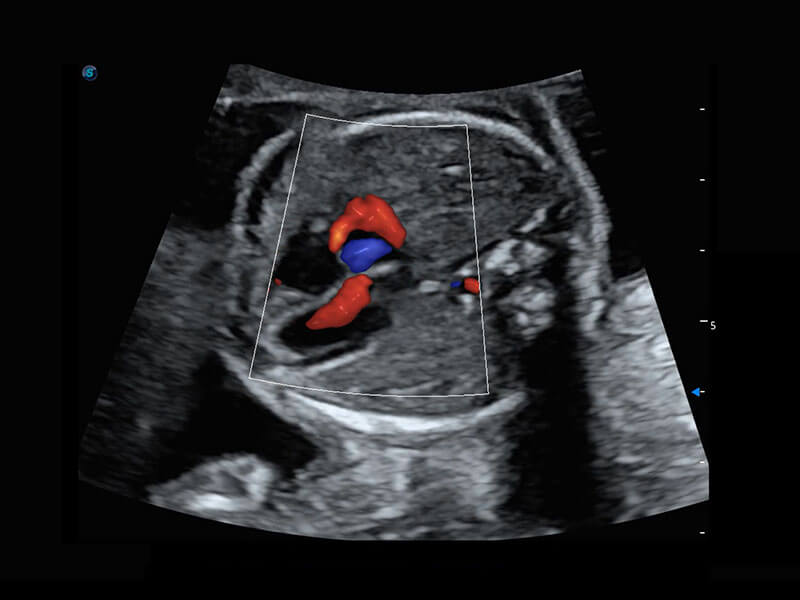

胎心筛查

P60搭载一系列胎儿心脏成像技术,实现精细的胎儿心脏评估。

• 四腔切面

• 四腔心血流

• 右室双出口

• 胎心容积成像